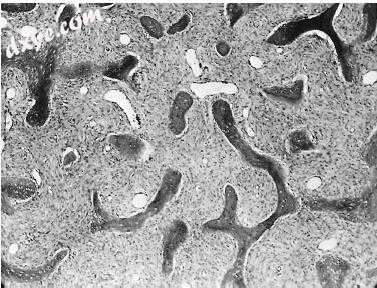

图-33. 纤维发育不良。 纤维血管基质中编织骨的不规则排列的骨针呈现轮状图案(×64)。

34.jpg